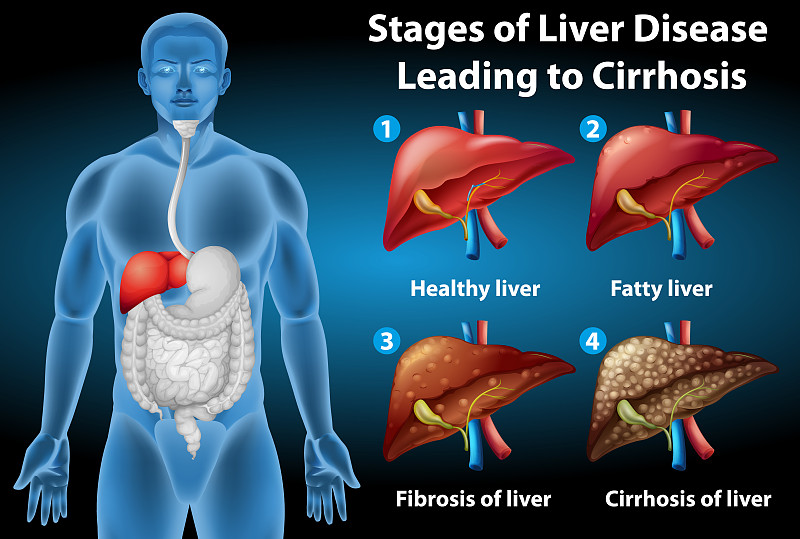

导致肝硬化的肝病阶段详情

导致肝硬化的肝病阶段详情